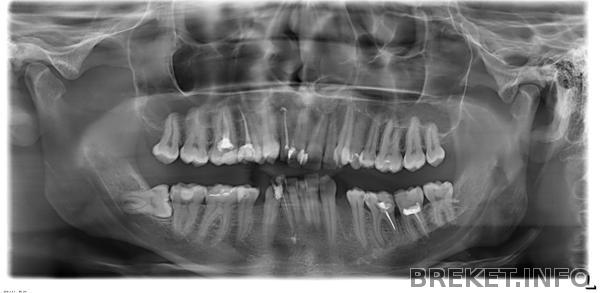

Это панорама до удаления лежачей 8-ки, но уже после удаления нижних четвёрок: